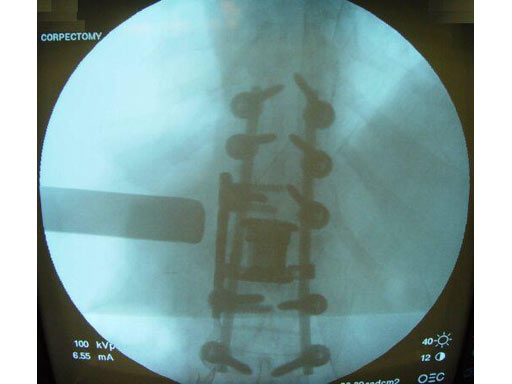

Case 1

Pathology: 68 - year- old male sustained a high energy C-type shear fracture of the L1 vertebra after a fall off of a bridge. The patient had received posterior fixation three weeks before this accident, but still displayed intractable leg pain. The posterior fixation consisted of Dual - Opening USS pedicle screws at T10 -T12 and L2- L3. The preoperative x- rays and MRI showed that the patient had some slippage at the L1- L2 disc and that there were still several pieces of bone impinging on the spinal canal.

Indication: Corpectomy of the L1 vertebral body.